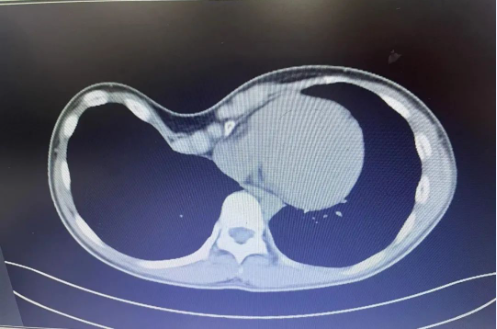

小冯随着年龄的增长,症状愈发严重,父母焦急万分,带着小冯到我院胸心外科就诊。胸心外科团队通过完善相关检查,发现小冯胸廓向内凹陷成漏斗状,且凹陷最深处偏向右侧,漏斗指数FI>0.3,评估为重度畸形。

通常漏斗胸最佳手术时间是6-12岁,而小冯已经15岁,骨骼架构基本定型,骨骼柔韧度较差,畸形严重且特殊,矫形难度剧增。团队考虑到对该患者采用目前我院较成熟的“NUSS(漏斗胸微创矫正术)”,此手术是漏斗胸最常采用的手术方式,但需进入胸腔,小冯胸腔内手术操作空间小,有损伤心脏和大血管的风险,主任李祥带领团队多次深入探讨和研究,为小冯制定了充分详细的个性化手术方案,征得家属同意后,决定对小冯实施微创“wang”手术,此手术不需进入胸腔,完全在胸腔外操作,大大降低了手术风险又可以达到矫形效果。